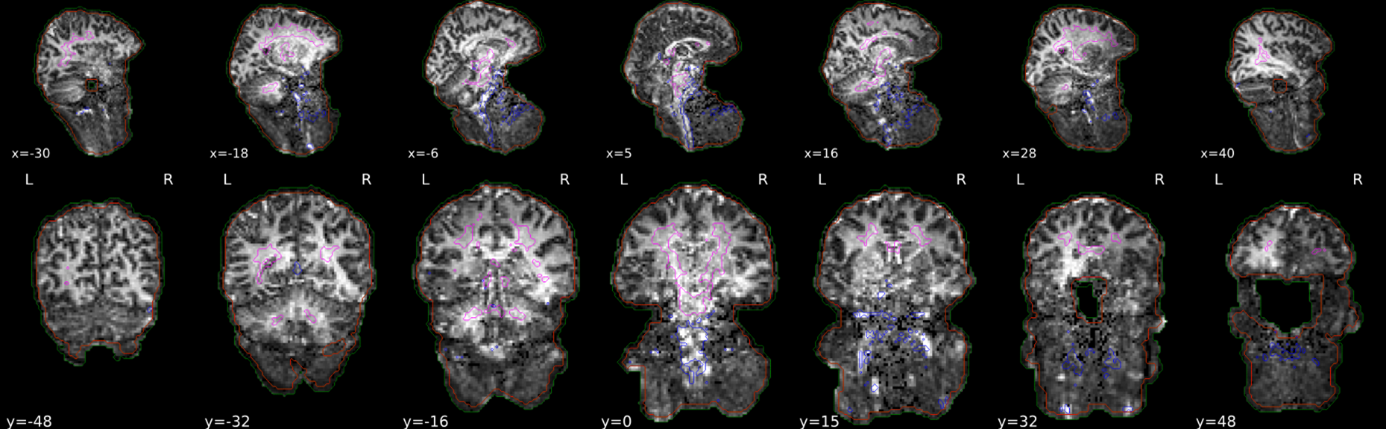

The below command was running fine without erros but produced weird looking output under the functional tab for “Brain mask and (anatomical/temporal) CompCor ROIs” (see screenshot).

As far as I could interpret this, brain was detected at the neck area… Is this normal or can I ignore this?